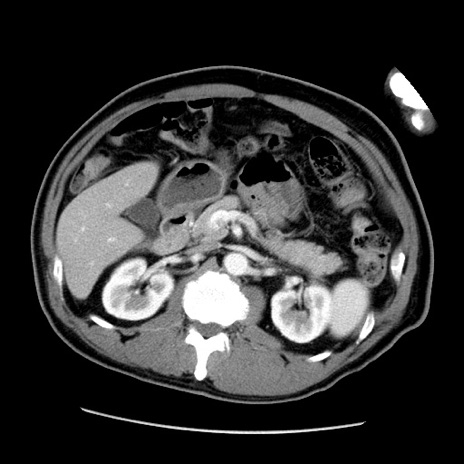

症例22(横断像)

【症例】50歳代男性

【主訴】腹痛

【現病歴】AVMからの被殻出血のため回復期リハ病棟入院中。 本日午後3時頃急に下腹部痛が出現した。

【既往歴】AVM、被殻出血、虫垂炎、高血圧

【身体所見】意識晴明、左半身不全麻痺、会話の理解は良好、36.5°C、腹部:膨隆、全体に板状硬、下腹部正中に圧痛点あり、反跳痛-、筋性防御不明、右下腹部にope scar

【データ】WBC 9400、CRP 0.06